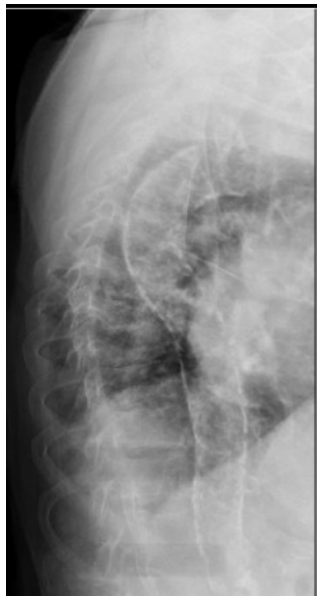

Paciente de 40 anos, do sexo masculino, portador de doença renal crônica secundária a GESF, em hemodiálise há dez anos, com queixa de dor óssea e prurido. Relatava dieta adequada, Estava em uso de carbonato de cálcio 2 cp no café, almoço e jantar; calcitriol 0,25 2cp/dia. Peso seco de 85 kg, Kt/V 1,0 e banho [Ca+] 3,0; trazia os seguintes exames: PTH de 790, fosfatase alcalina 462, cálcio de 9,5, fósforo de 6,7 e raio X a seguir.